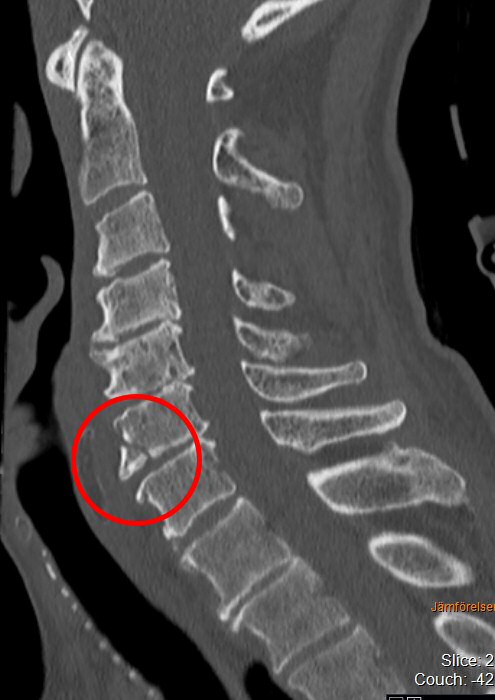

Teardropfrakturer

Typiskt äldre patient med degenererad halsrygg som fallit på pannan berusad. DT med diskreta fynd, kan vara helt normal, visa extensions teardrop (se bilder nedan) eller distraktion i disk. Kan vara mycket instabil.